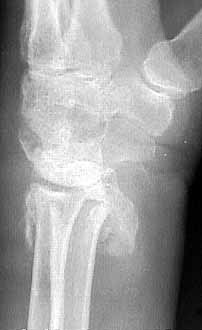

Seeking advice on management of 1 month old untreated distal radius fracture in non dominant hand of a 64 years old watchman. Pictures and xrays attached.

Lateral